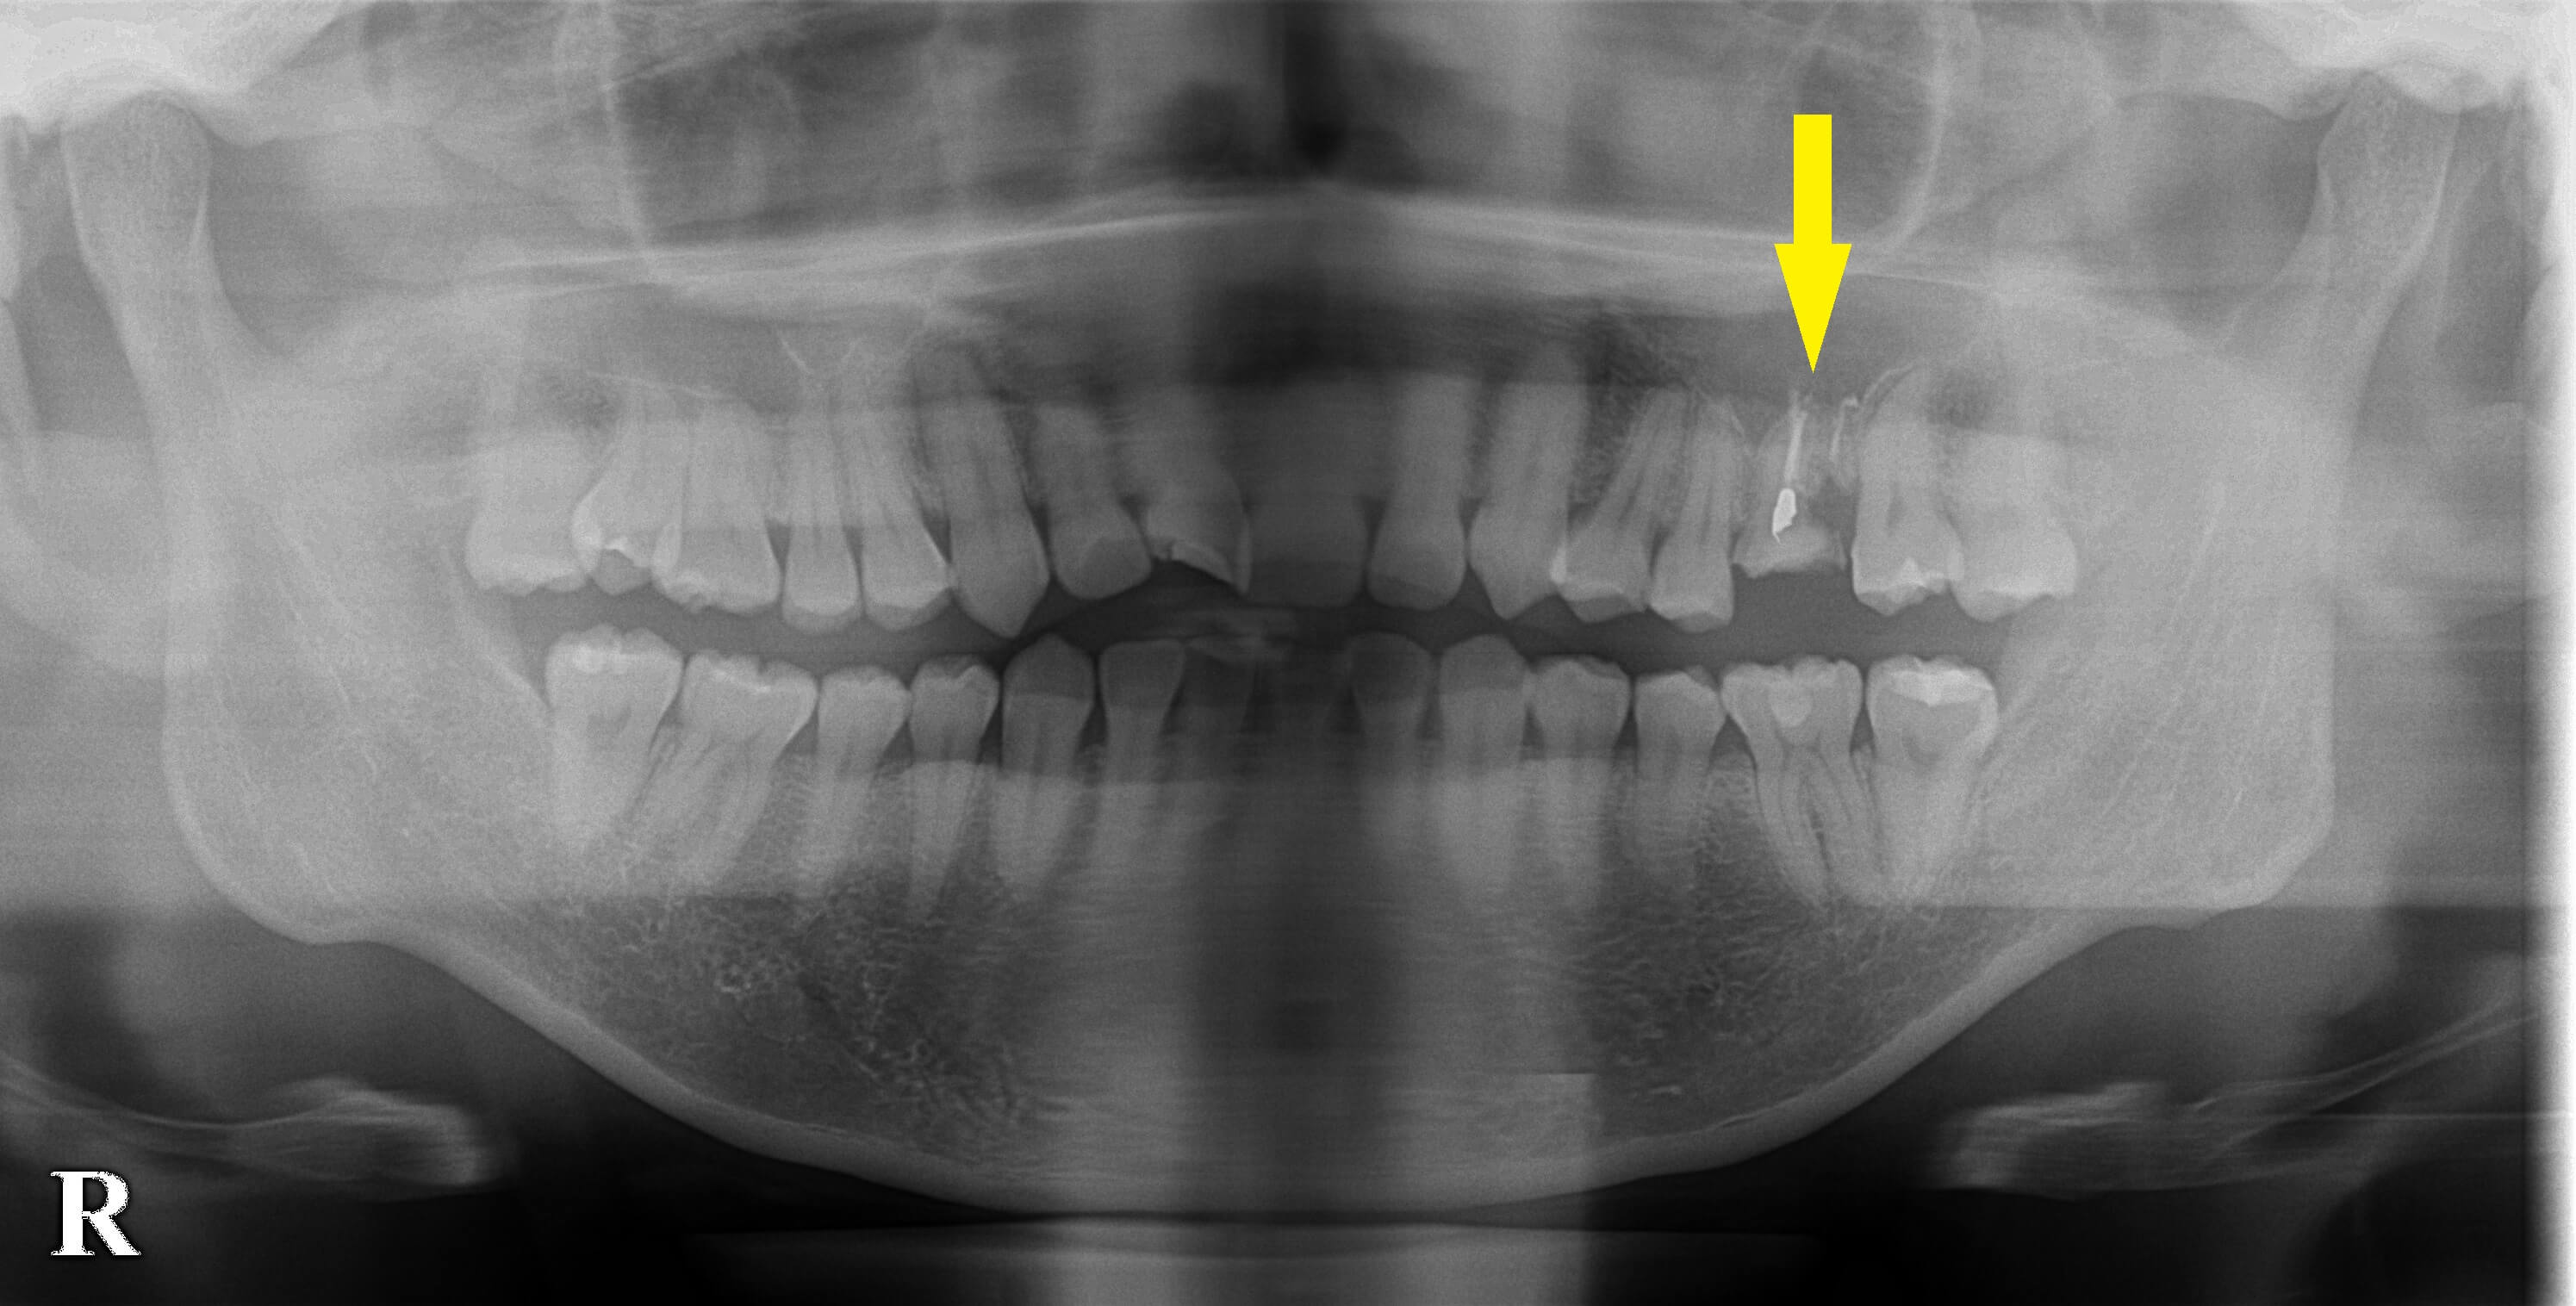

CTを撮ってみると、歯の根っこが、上顎の上方の空洞に突き抜けており、抜歯したら骨に穴が空いてしまう状態でした(下の写真2段目左右)。